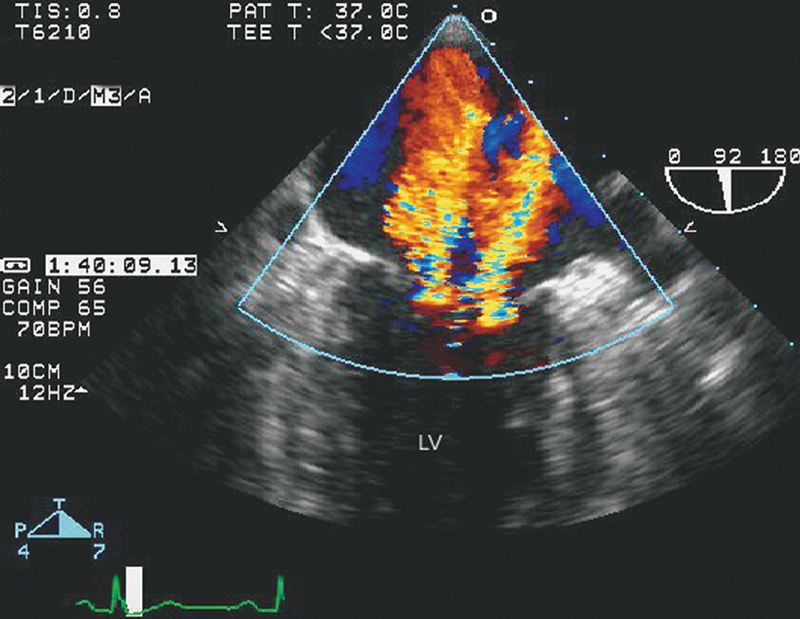

فحوصات تشخيصية لبعض امراض القلب والشرايين التاجية